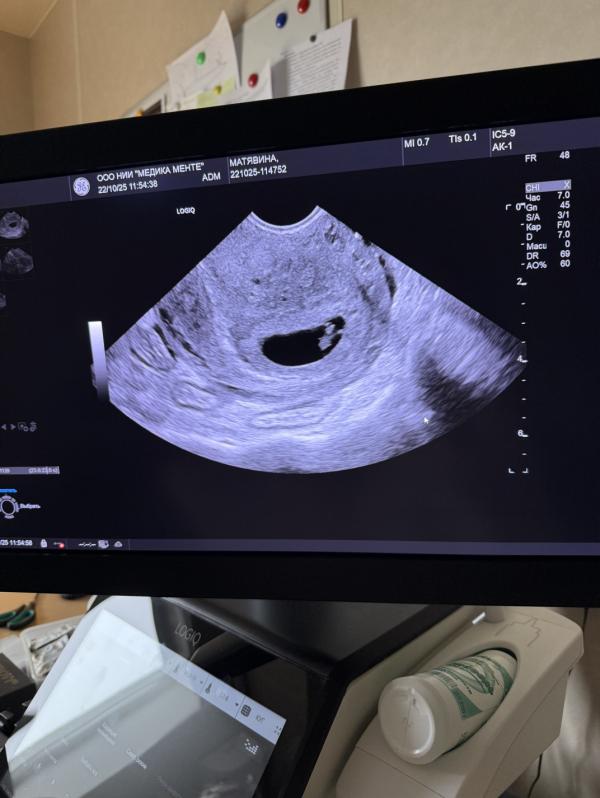

Первое УЗИ при беременности: 6 недель и сердцебиение

Бусинка на месте, сердечко пульсирует🙏🏻🥹ждём тебя наше счастье❤️❤️❤️

УЗИ делала вчера по срокам 6,3- аппарат насчитал 6,5))